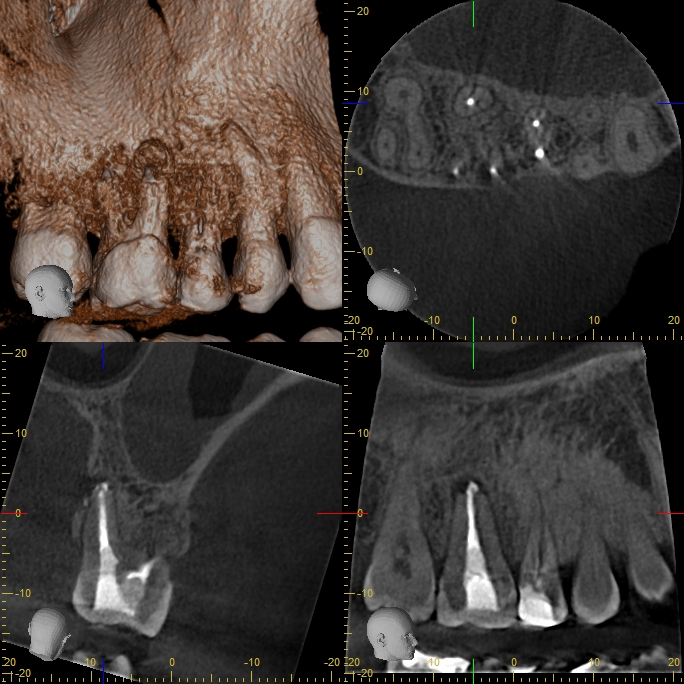

xyzview_20160929_185722

Revision nach Resektion